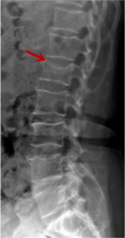

利器一:X線/DR

腰椎X線片作為最基礎(chǔ)的影像檢查手段,利于X線穿透人體組織后成像,以其快捷、直觀、價(jià)格低廉的特點(diǎn),X線檢查主要包括腰椎正側(cè)位、雙斜位以及過伸過屈位。主要用于觀察腰椎骨骼的情況,如椎體是否有骨折、骨質(zhì)增生程度、生理曲度的變化、椎體移位的情況等。然而,X線檢查也有它的局限性,無法判斷是骨折的新舊,對(duì)于椎體內(nèi)部結(jié)構(gòu)和周圍肌肉韌帶組織(如脊髓神經(jīng)、椎間盤、韌帶等)的顯示不佳,另外X線作為有輻射檢查,孕婦及嬰幼兒謹(jǐn)慎選擇。

箭頭提示腰1椎骨折

箭頭提示腰3椎體滑脫